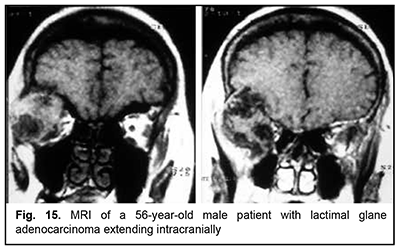

The most aggressive growth and course among epithelial lacrimal gland tumors is seen in adenocarcinomas (Fig. 15). Adenocarcinoma had the highest rate of mortality (67.7%) among PELGT with involvement of the cranial cavity and cerebrum, followed by adenoid cystic carcinoma (47.7%) and pleomorphic adenoma (37.5%). In addition, although pleomorphic adenoma of the lacrimal gland is a benign tumor, its rate of mortality was 9.1%. This could be explained by the fact that, like malignant tumors, these benign tumors tend to recur and transform to adenocarcinomas, adenoid cystic carcinomas and pleomorphic adenomas. The recurrence rate for malignant PELGT was 47.5%, and for benign PELGT, 23.5%. It is noteworthy that we have observed recurrences of pleomorphic adenoma even after 20 years after primary tumor excision.